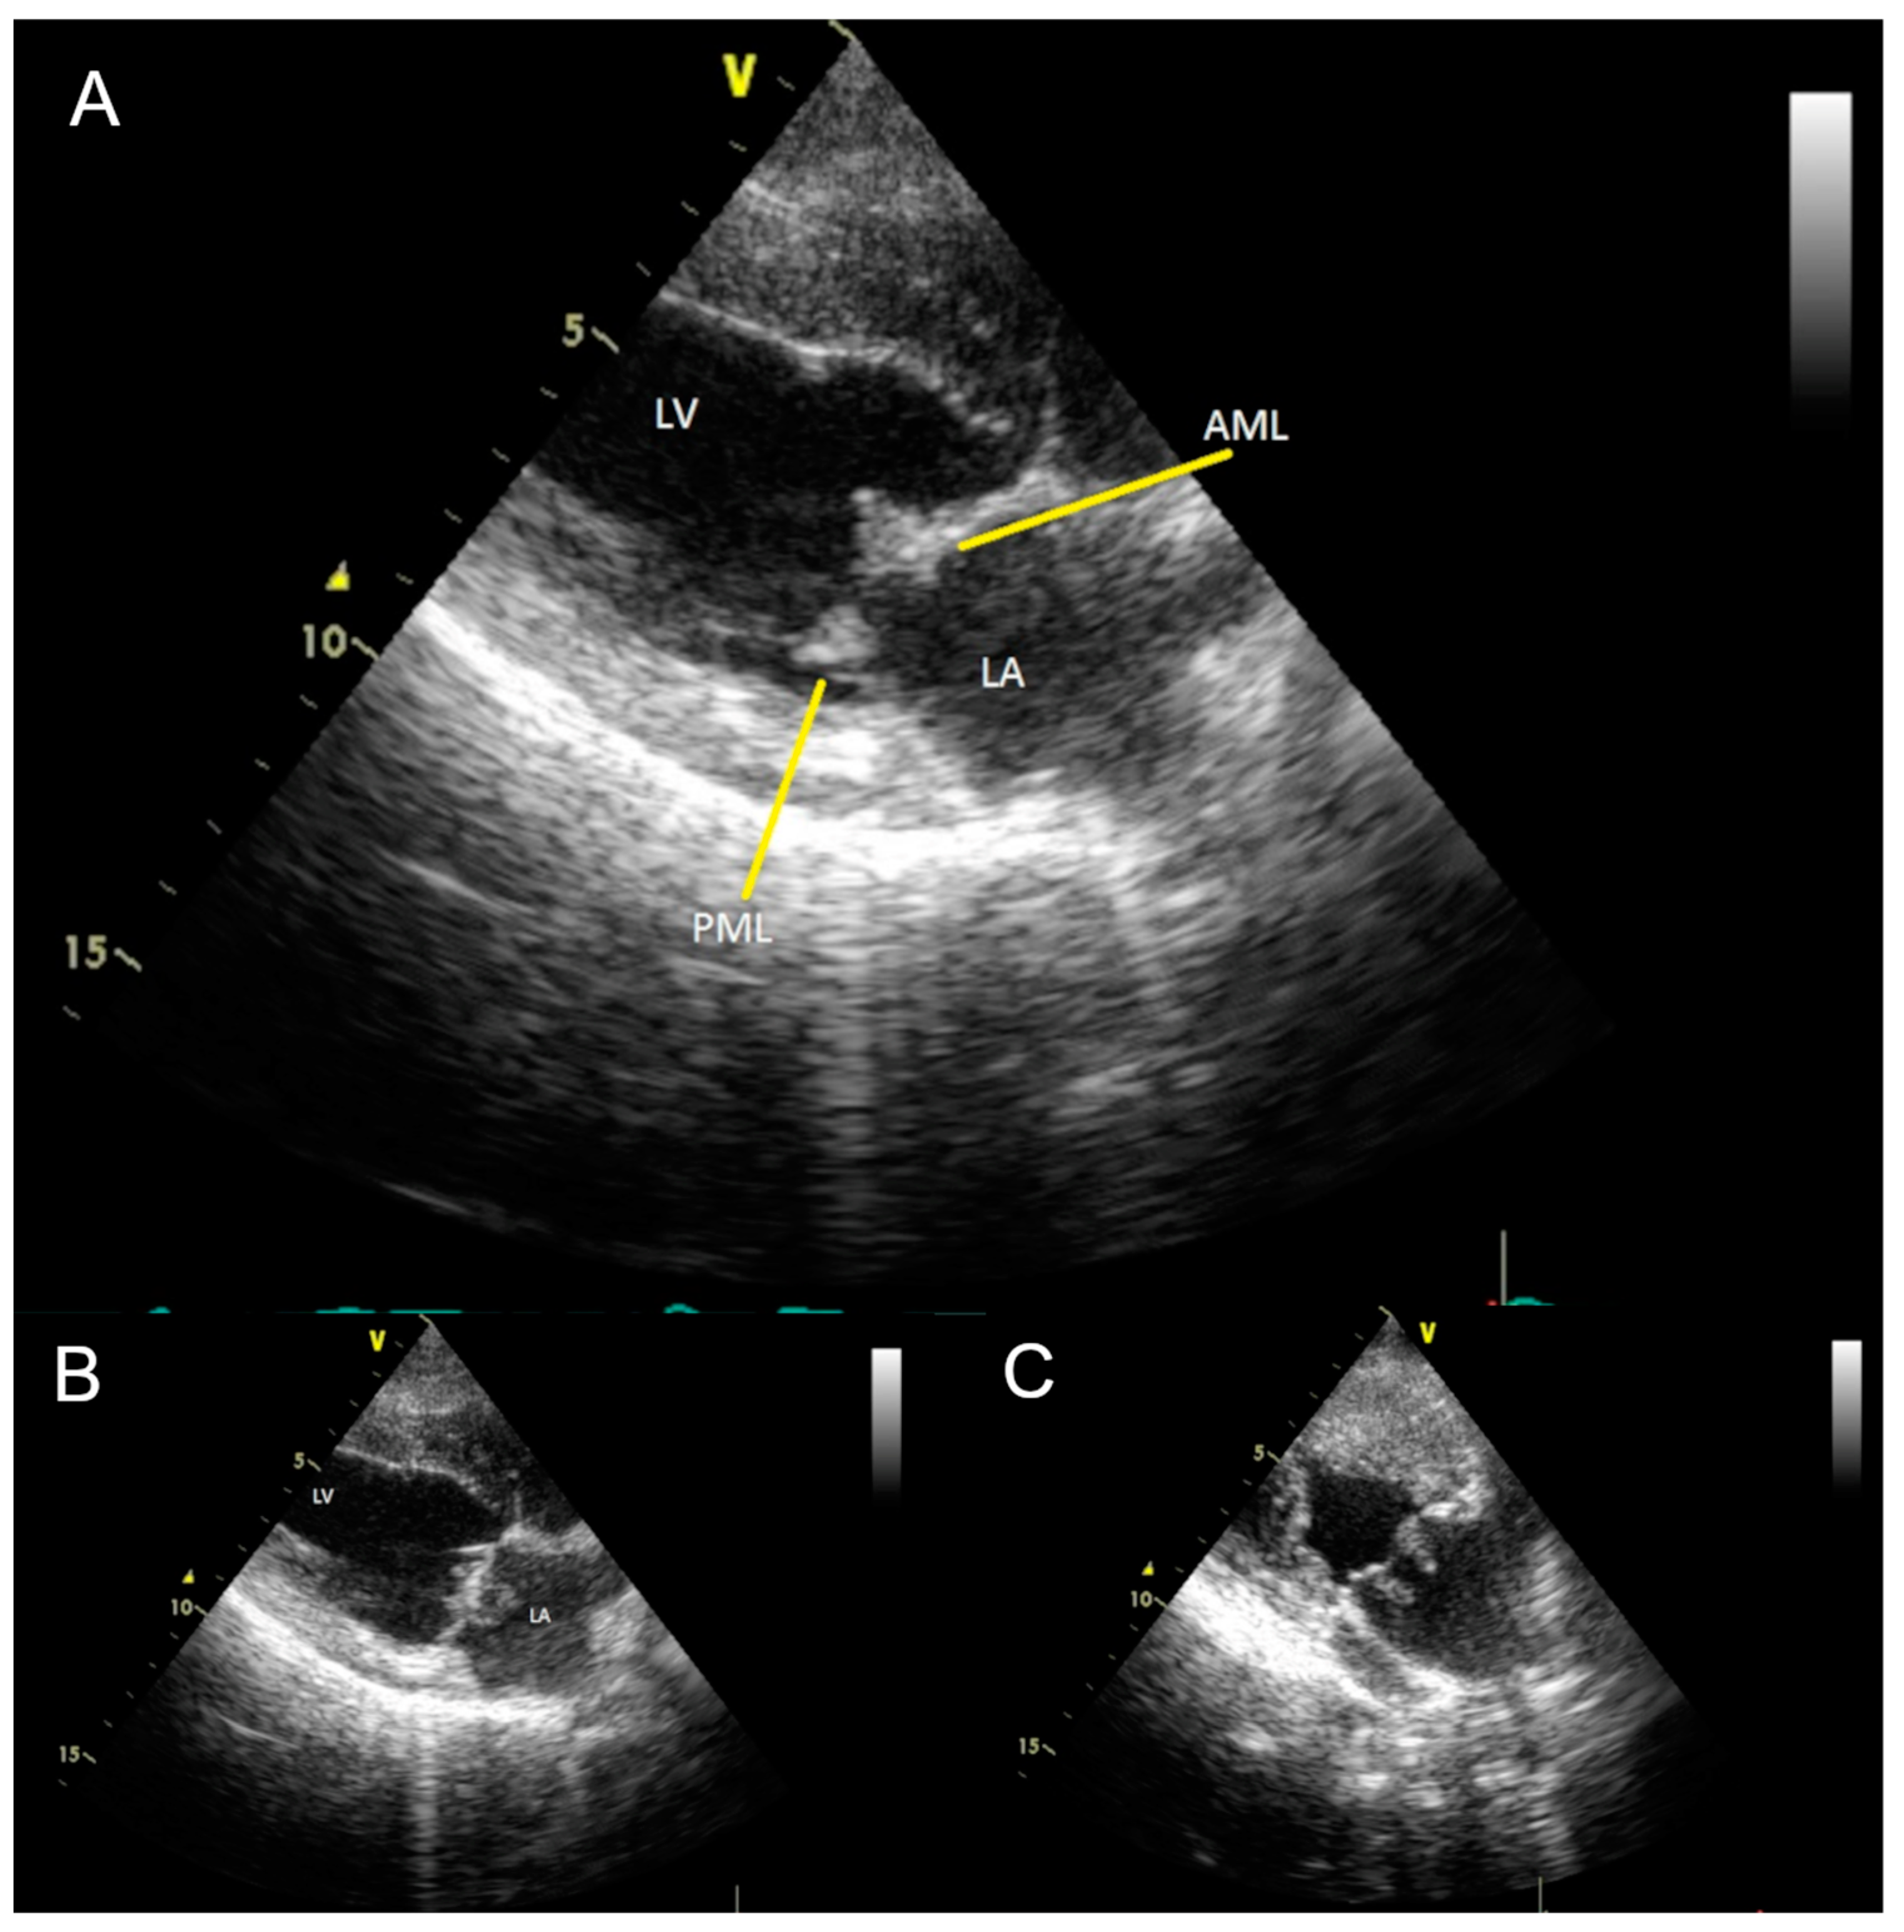

1. Case Presentation